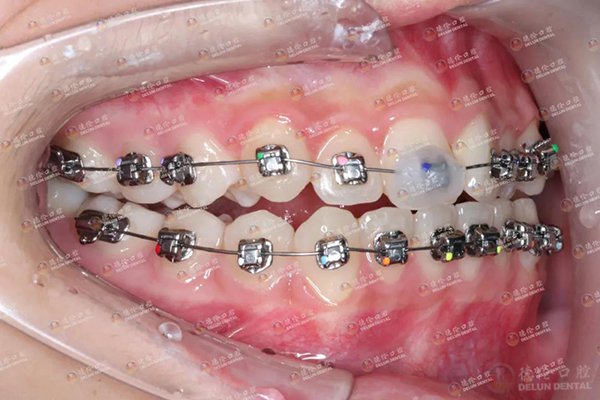

妹妹采用的是发展比较早,技术比较成熟的传统金属自锁矫治器